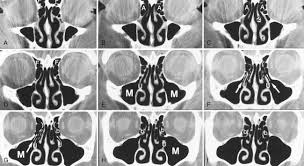

Each image highlights and labels the sinuses in coronal and sagittal view. The nasal septum divides the cavity into two cavities, also known as fossae. The nasal cavity forms part of the aerodigestive tract. The nasal cavity is divided in two by a vertical fin called the nasal septum. The nasal septum divides the nasal cavity into two chambers.

The nasal septum divides the cavity into two cavities, also known as fossae. Nasal cavity and sinus tumors are usually treated with surgery. Carlson nasal, oral & laryngeal cavities, illustration ss21310241. Explore over 200 cadaveric images right at your fingers, providing a new supplemental interactive experience for dissection labs. In front of the face, the nasal cavity opens with nostrils, behind it through the choana, it communicates with the nasopharynx. The nasal cavity forms part of the aerodigestive tract. The cavity of the nose (cavum nasi) is divided by the septum of the nose into the right and left halves. In addition to being an integral part of the respiratory system, your nose also serves as the organ of olfaction or smell. The nasal cavity (or nasal fossa) is a large air filled space above and behind the nose in the middle of the face. Radiology axial cadaver images nasal cavity dissection video. Inferior, middle and superior nasal conchae (turbinates) superiorly: Nasal cavity definition, anatomy, functions, diagrams. The nasal septum divides the nasal cavity into two chambers.

Inferior, middle and superior nasal conchae (turbinates) superiorly: nasal cavity labeled. Each image highlights and labels the sinuses in coronal and sagittal view.